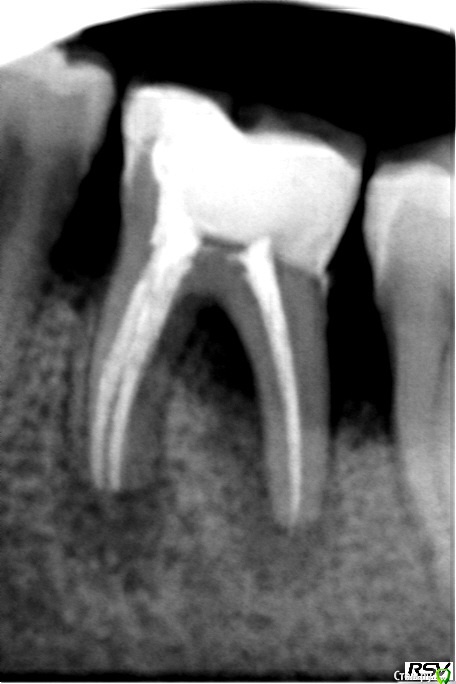

Ирина Игоревна Опубликовано 10 марта, 2015 Поделиться Опубликовано 10 марта, 2015 В сентябре в клинику обратилась пациентка,поставлен диагноз хр. пульпит.Протокол лечения: коффердам,обработка каналов ProFile 15.04,20,04,25.04,25.06,35.04,40.04. Упор не доходя 1мм 40.02. Медикаментозная обработка 3%р-ом гипохлорита натрия, после каждого инструмента замена раствора. Финишная мойка гипохлоритом натрия с активацией УЗ,дистиллированная вода,40%р-р лимонной кислоты с активацией УЗ,дистиллированная вода,спирт.Обтурация методом латеральной компакции,силлер АН+.В это же посещение постоянная реставрация "Филтек 550". Жалоб сразу после лечения не предъявляла.Спустя пол года обратилась вновь с жалобой на припухлость десны.Сделала снимок и в легком шоке.В чем может быть причина такой резорбции?недопломбировка?может недомыла,хотя мою всегда на совесть.Или же проблема в пародонте.Перкуссия отрицательна.Слизистая гиперемирована,отечна.Пока отпустила с каласептом Ссылка на комментарий

Паращук Роман Опубликовано 11 марта, 2015 Поделиться Опубликовано 11 марта, 2015 Имхо разная проекция,контраст + наложение клампа дали визуальную разницу. Ссылка на комментарий

DR.P Опубликовано 16 марта, 2015 Поделиться Опубликовано 16 марта, 2015 отсутствие контактов дало резорбцию перегородок, соответственно дальше пошла перегрузка зоны бифуркации - ушла и она. Меня еще интересует антагонист - не импантат случайно? Ссылка на комментарий